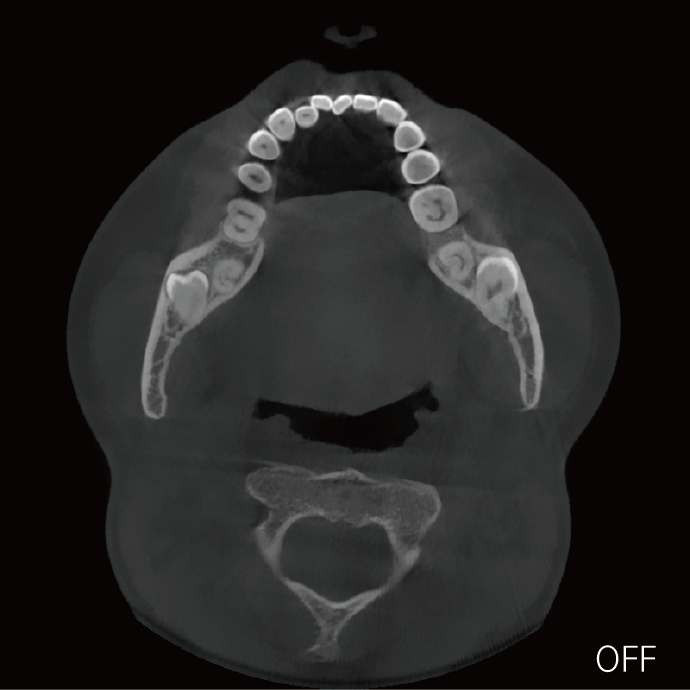

超能去伪 至臻影像

支持局部超清三维显示

可根据临床需求任意调整成像区域大小实现局部超清三维显示